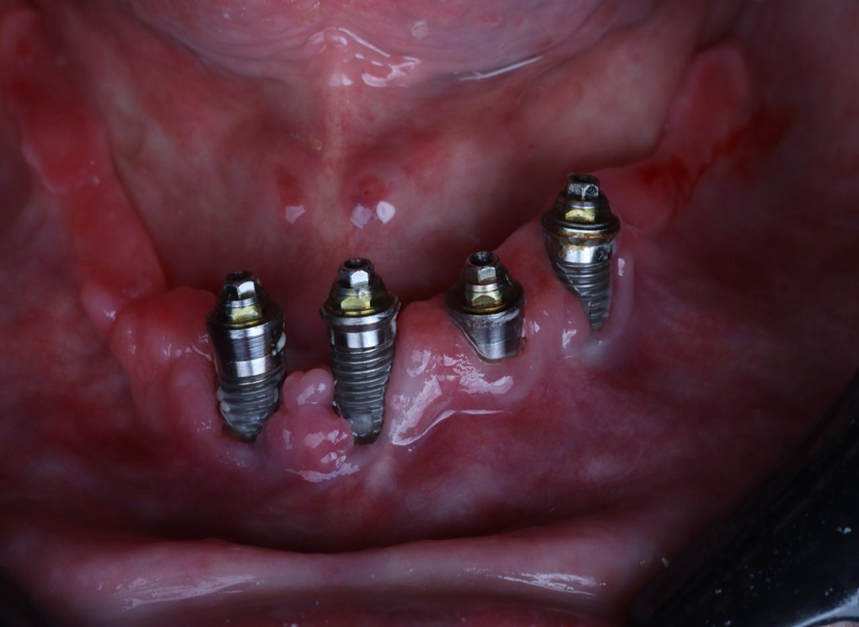

Paciente de 62 anos, do sexo feminino, sem comorbidades e história médica pregressa, apresentava severa reabsorção óssea em regiões anteriores e posteriores da mandíbula devido a uma peri-implantite (Figuras 1A e 1B). Feita a remoção dos implantes, a paciente optou por utilizar uma prótese total mucossuportada até a nova intervenção com prótese do tipo protocolo inferior. Após seis meses, a mandíbula encontrava-se cicatrizada (Figura 2). Como parte do protocolo diagnóstico, foi realizada tomografia computadorizada pela técnica do duplo DICOM. Com a severa perda óssea em região anterior de mandíbula, optamos por realizar a cirurgia de forma guiada, aumentando a previsibilidade e precisão da cirurgia. Os arquivos obtidos foram exportados para o software CoDiagnostiX, possibilitando a realização do planejamento reverso e o subsequente posicionamento virtual dos implantes (Figura 3). Com base no planejamento, optou-se pela instalação de quatro implantes Implacil Osstem CM AR Due Cone (3,5 x 7 mm), associados a mini-cônicos de 1,5 mm (Figuras 4A, 4B, 4C, 4D e 4E). A partir da tomografia da prótese da própria paciente, confeccionaram-se duas guias cirúrgicas: uma guia de pino de fixação (Figura 5) e uma guia de fresagem para a instalação dos implantes (Figura 6). Durante o procedimento cirúrgico, inicialmente foi posicionada a guia de pino de fixação para fresagem dos pinos de fixação e orientação da sequência cirúrgica (Figura 7). Após essa etapa, a guia foi substituída pela guia de fresagem dos implantes (Figura 8), utilizada para a fresagem e inserção dos implantes planejados (Figura 9). Concluída a instalação, optou-se por seguir o fluxo analógico, com a adaptação dos mini-cônicos 1.5 mm (Figura 10), realização da transferência de moldagem com silicona de adição leve e sutura com fio absorvível Vycril 6-0. O guia inicial foi adaptado com broca Maxicut, possibilitando sua utilização como molde de orientação para o laboratório protético (Figura 11). Após a moldagem, foram posicionadas as tampas de proteção sobre os implantes. Na fase protética, transcorridas 48 horas do procedimento cirúrgico, foi realizada a prova clínica da barra metálica e dos dentes (Figura 12). Na etapa subsequente, 72 horas após a cirurgia, procedeu-se à instalação e entrega do protocolo mandibular inferior e radiografia prévia, reabilitando funcional e esteticamente a paciente em curto espaço de tempo (Figuras 13A e 13B).